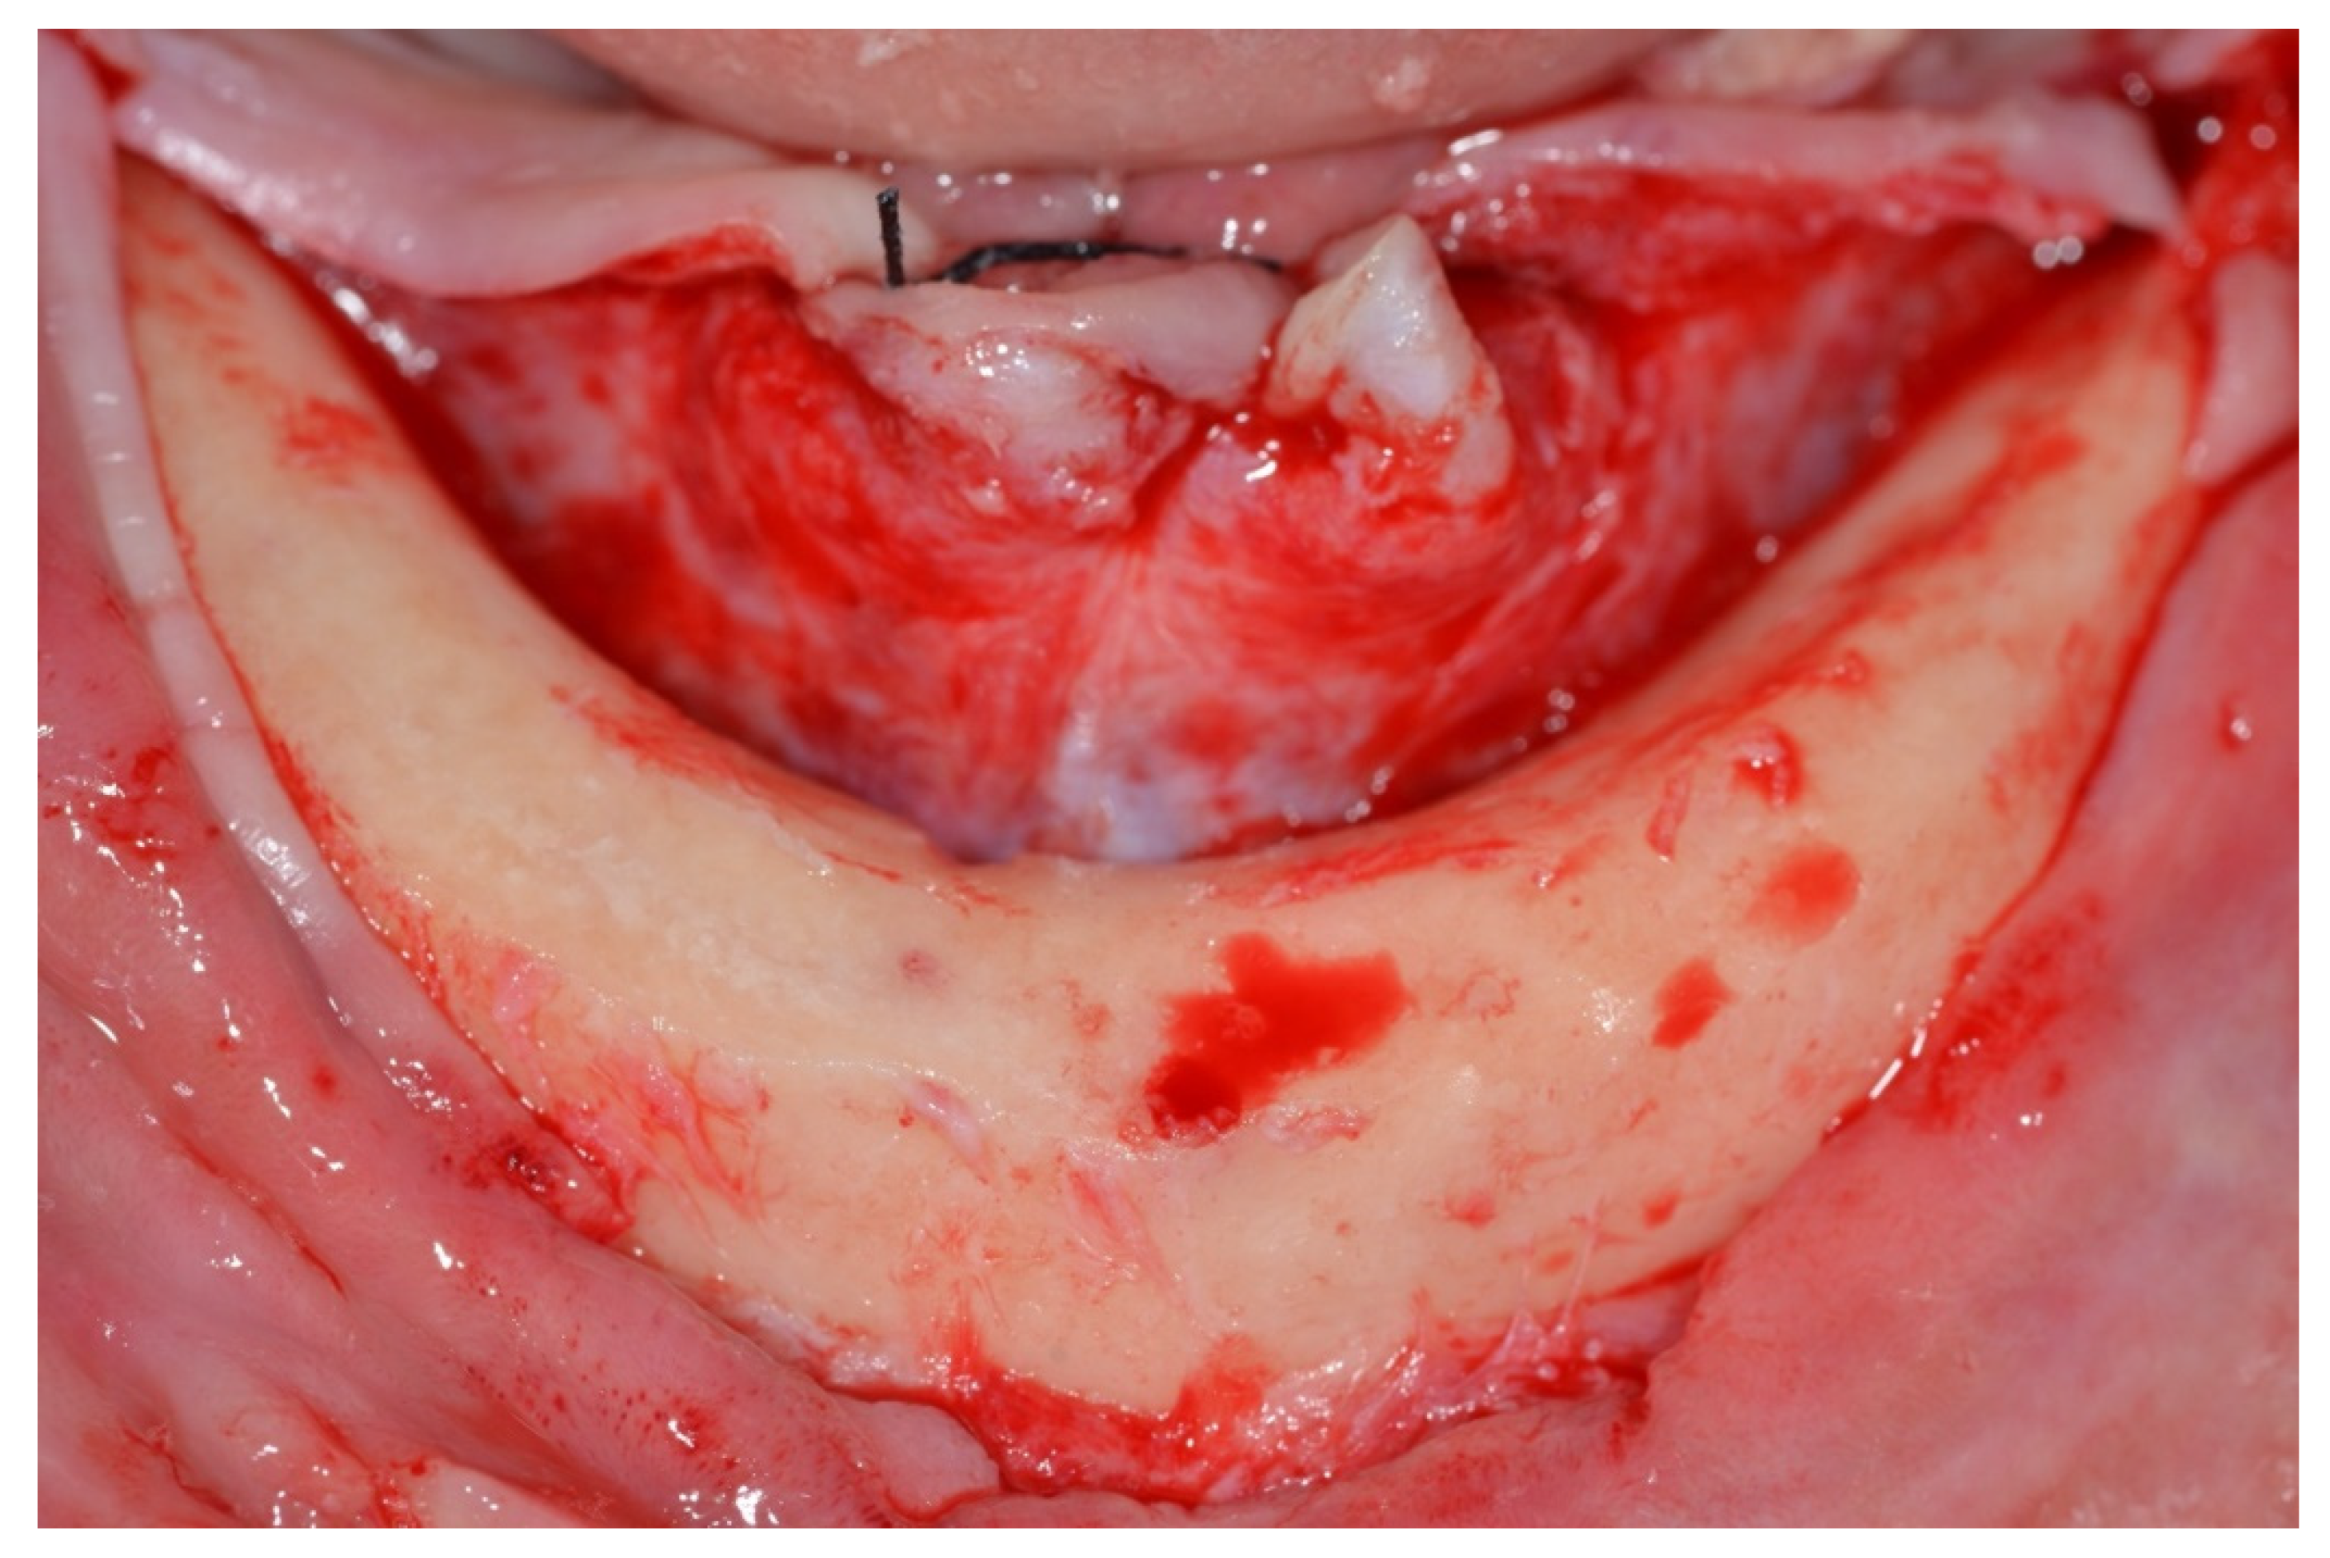

Surgical Protocol